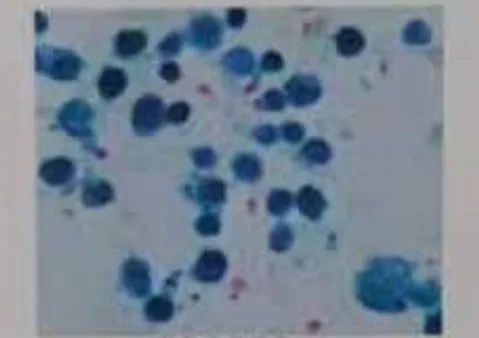

近日,长沙市妇幼保健院儿科急诊科接诊了一位4岁小女孩,她五官精致,却面如白纸,呼吸浅促,虚弱得没有力气说话。长沙市妇幼保健院儿科主任龚晓辉仔细查看患儿,发现她睑结膜、口唇、甲床均极度苍白,是典型的贫血貌。追问病史,家长说小朋友之前身体一直挺好的,就是最近这五天来,突然出现咳嗽、乏力,也不爱吃东西,脸色看着就不好了,就诊前两天更是粒米未进。情况十万火急,龚晓辉立即指挥抢救:紧急完善血常规、血型检查,交叉合血,准备为患儿输血,同时呼叫床旁彩超。超声结果很快出来:腹部、心脏均未见异常。没一会,医护人员就接到检验科危急值通知:血红蛋白仅21g/L!听到这个结果,在场所有人都紧张起来,这可是一个危及生命的数值。考虑过孩子存在严重贫血,但只有21g/L的血红蛋白还是让医生惊出一身汗,极重度贫血!情况太危急!龚主任再次分析病情:既往没有贫血情况,结合患儿年龄及平日饮食情况不支持营养性贫血;没有黄疸,酱油色尿,不支持溶血;没有肝脾淋巴结肿大等慢性贫血表现,没有皮肤粘膜出血,血小板不低,白血病等骨髓造血障碍也不支持,那就只有可能是失血了,而且存在急性失血!失血的部位到底在哪里呢?龚主任脑中划过一道亮光:听诊肺部是有湿啰音的,难道是肺泡出血?之前仅仅把它当作肺炎的表现了,必须马上完善肺部CT检查!影像结果弹出的一刹那,猜想得到了验证:真的是弥漫性肺泡出血。原来,血液是从肺部丢失了,考虑到“特发性肺含铁血黄素沉着症”可能性大,医护人员紧急联系病理科进行痰涂片检查,发现含铁血黄素细胞,支持了这一判断。在完善检查排除结核感染、血管炎、狼疮等各种感染及继发因素后,医护人员为患儿输血纠正贫血,使用糖皮质激素抑制免疫治疗。病情好转后,许继志主任给小朋友做了一次肺泡灌洗,灌洗液行普鲁士蓝染色,发现满屏的含铁血黄素细胞,特发性肺含铁血黄素沉着症确诊。

普鲁士蓝染色 图源:长沙市妇幼保健院订阅号